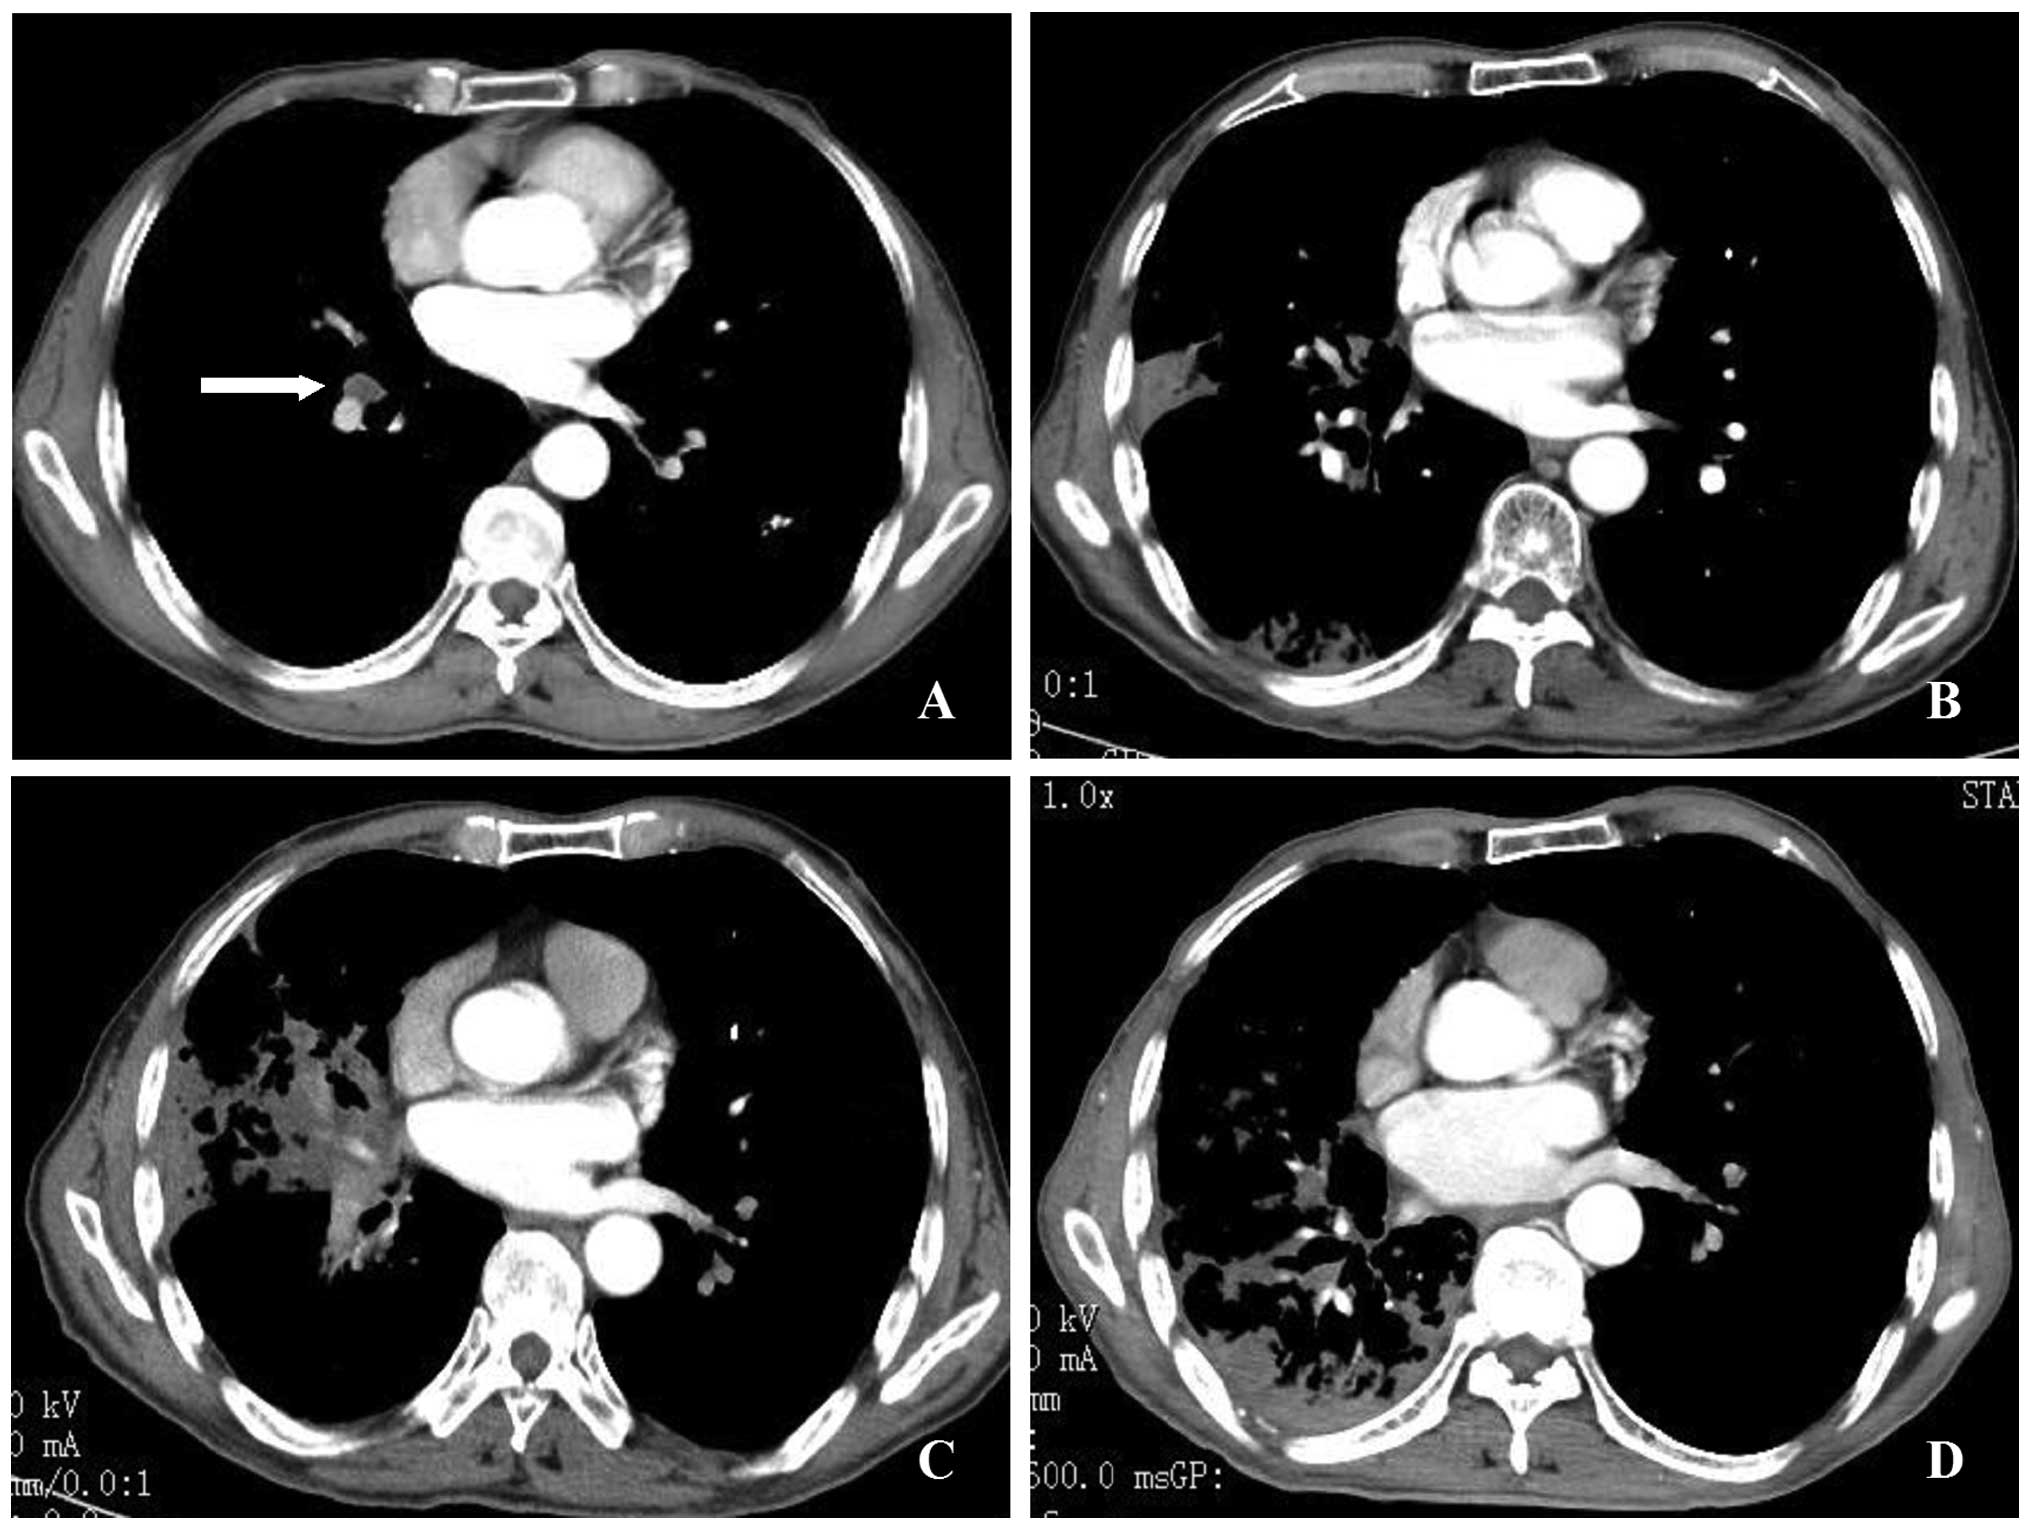

Small Cell Lung Cancer Sclc Imaging Practice Essentials